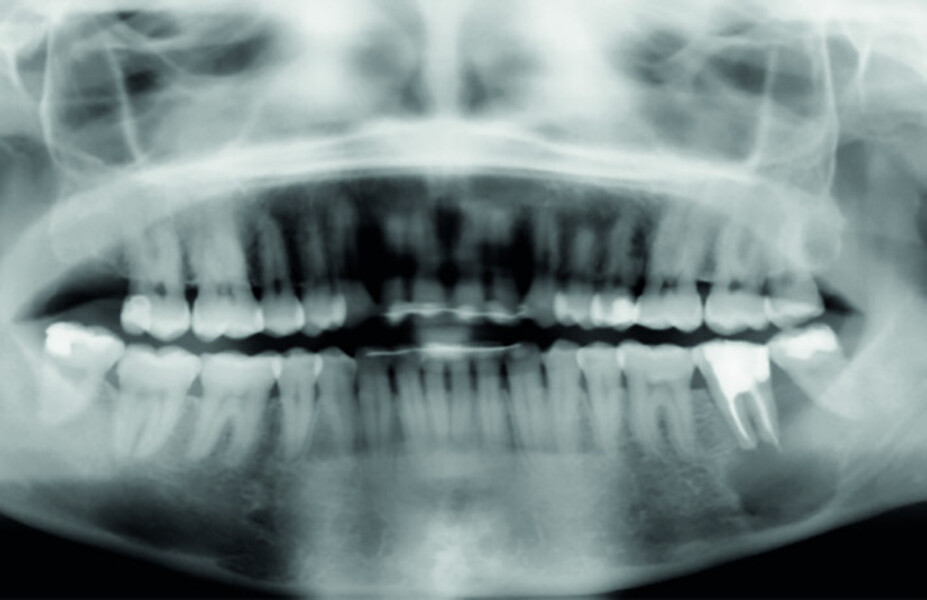

Fig. 4: Pre-op CBCT scan, pseudo-panoramic view.

Fig. 15a: Radiograph: Pre-op panoramic.